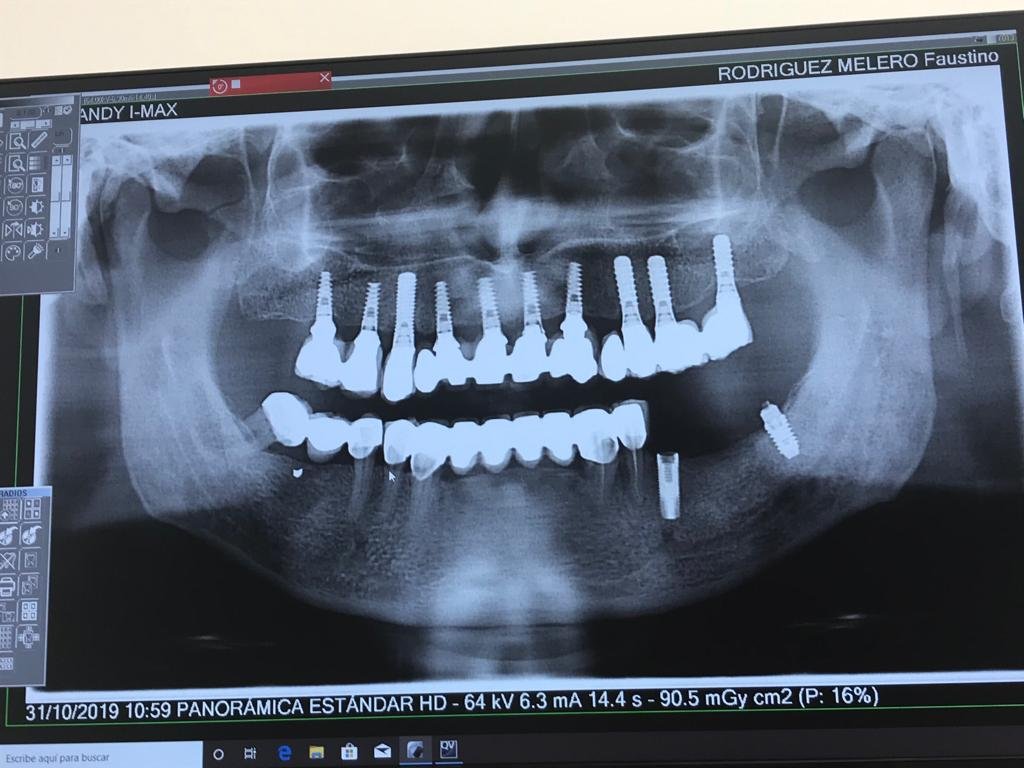

Buenas tardes Necesito saber si reconocen el implante de la radiografía. Fue colocado hace años en una clínica Dental Line en Bilbao, calle Zabalbide que ya no existe. En caso [...]

Tiene flojos los implantes superiores derechos colocados hace más de 20 años

Buenos días. Quería rehabilitar el implante del 2.6. Colocado en dentalis hace 12 años. Me podéis decir cuál es? Gracias.

Me gustaría saber qué implantes son los que vemos en posición de 36 y 46. La paciente se los colocó en otra clínica y solicita su rehabilitación. Muchas gracias